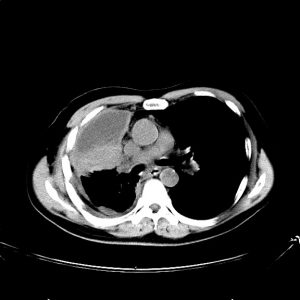

Παραδείγματα πότε μπορεί να βοηθήσει η εξέταση (ΕBUS) στη διάγνωση